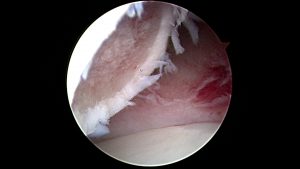

Durch einen kleinen Schnitt wird ein Arthroskop, das mit einer Lichtquelle und einem Kamerasystem verbunden ist, in das Gelenk eingeführt. So kann die Gelenkshöhle hochauflösend und stark vergrößert eingesehen und alle Strukturen im Detail dargestellt werden. Selbst kleine Veränderungen am Knorpel oder der Gelenkstruktur, die mit bloßem Auge oft gar nicht sichtbar sind, können schnell erkannt werden. Gleichzeitig können durch eine zweite kleine Öffnung Instrumente eingeführt werden, um die Erkrankung gleich zu behandeln.